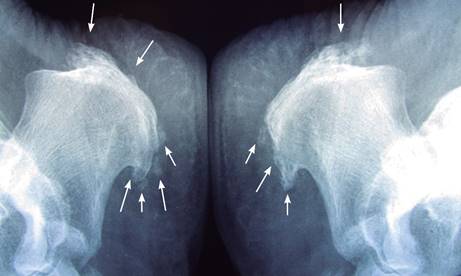

Mujer de 79 años, con antecedentes de obesidad, diabetes mellitus tipo 2 de 10 años de evolución, controlada con hipoglucemiantes orales; hipertensión arterial de siete años controlada con bloqueador de receptor de angiotensina 1; manejada desde hace cinco años con estatinas por hipercolesterolemia. Acude por dolor crónico en ambos talones, tanto a nivel plantar como en su cara posterior durante los últimos ocho meses, dificultando de manera importante la marcha. A la exploración: paciente obesa con índice de masa corporal (IMC) de 33.2, tensión arterial 150/90 mmHg; frecuencia cardiaca 80 latidos/min; frecuencia respiratoria 18 respiraciones/min. Postura: simetría en plano frontal, retropié pronado 14o bilateral; en plano sagital: cifosis dorsal, hiperlordosis lumbar, basculación pélvica, abdomen prominente, semiflexión de rodillas de 10o; cráneo cara y cuello sin alteraciones, tórax normal, abdomen doloroso globoso a expensas de panículo adiposo sin visceromegalias; los arcos de movilidad de miembros superiores normales, manos sin nódulos de Heberden; arcos de movilidad en cadera limitados por contractura de flexores de cadera en los últimos 15o de extensión resto normales, rodillas con contractura de flexores (isquiotibiales y tríceps sural limitando la extensión pasiva a menos 10o, no dolorosas a la movilización activa y pasiva, tobillos y pies con aumento de volumen de cara posterior de ambos talones (Figura 1), engrosamiento bilateral de tendón de Aquiles a nivel de su inserción dolor localizado a nivel de tuberosidad interna de ambos calcáneos con irradiación a zona plantar interna al momento de efectuar dorsiflexión de dedos de los pies. Al plantoscopio se observa pie plano grado III y hallux valgus bilateral de 20 grados; signo de Godet hasta tercio medio de ambas piernas, sensibilidad discretamente disminuida en ambos tobillos y pies, pulsos arteriales y llenado capilar normal. El cuestionario VISA-A3 utilizado para valorar la severidad de la tendinopatía del tendón de Aquiles mostró resultados de 28 (valor óptimo 100). Con diagnósticos de: fascitis plantar bilateral, deformidad de Haglund bilateral, entesopatía de inserción del tendón de Aquiles severa bilateral y neuropatía diabética, sin osteartritis generalizada. Se solicitan radiografías laterales de ambos tobillos y pies (Figuras 2 y 3). Los exámenes de laboratorio de velocidad de sedimentación globular y proteína C reactiva con resultados dentro de límites normales, glucosa 140 mg/dL, creatinina y ácido úrico dentro de límites normales. Se prescribió aplicación de crioterapia a talón (20 minutos TID), zapatos para diabético sin talón, con plantillas integradas en plastazote con soporte de arco longitudinal de 21 mm, ejercicios moderados de estiramiento de fascia plantar y de tríceps sural; tramadol en gotas a dosis de 10 mg cada ocho horas y paracetamol 500 mg, cada ocho horas, además de programa de reacondicionamiento físico en ergómetro de bicicleta fija, iniciando con 10 minutos/día con incrementos de cinco minutos semanales, además de control de disminución del peso corporal y manejo por endocrinología. Se explicó a la paciente que de no existir mejoría en un lapso de 10 semanas, la cirugía estaría indicada. En el seguimiento la paciente disminuyó 6 kg de peso, sus controles de glucosa mejoraron, con mejoría del dolor e incremento de velocidad y distancia de marcha, por lo que continúa con tratamiento conservador.

Figura 2: Radiografía lateral de ambos calcáneos, se observan calcificaciones (flechas) en: tendón de Aquiles, prolongación del plantar delgado, inserción del flexor corto de los dedos (cuadrado carnoso de Silvio) e inserción de la fascia plantar en la tuberosidad interna del calcáneo.